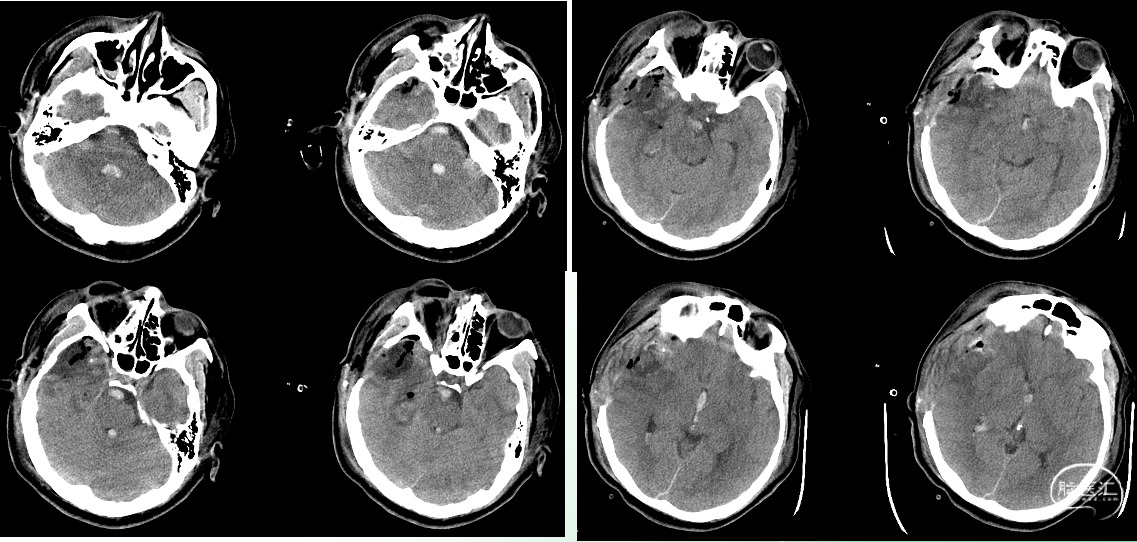

入院时影像

急诊颅脑CT+三维重建:

颅脑锐器损伤并异物存留,异物由右侧眼眶刺入颅内;右侧额颞叶挫裂伤并血肿形成;蛛网膜下腔出血;脑室系统较多积血;右侧额颞顶部少量硬膜下积血

术后即时影像